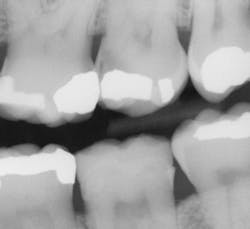

There is a direct ROI when using this sensor compared to older digital sensors or even film. I can appreciate a significant improvement in identifying interproximal and recurrent caries on patients that I thought were completely healthy. It honestly is scary what I had been missing with the previous generation of digital sensors. I also like Schick 33's presets called clinical-task-specific mapping. I can click on a preset and images automatically default to the setting I need -- general dentistry, endodontics, periodontics, or restorative dentistry. Once the image is captured, I can instantly adjust sharpness by moving my cursor left or right over the graphical slider.

Prior to digital sensors, I often would inform patients that "I am not sure how deep the cavity is, but once we start the recommended procedure, I will be able to assess the situation.” Today, with the clarity provided by this sensor, I find myself having the opportunity to explain my findings more objectively to my patients. As a general dentist, I feel responsible for providing all my patients the best comprehensive exam possible. This sensor allows me to diagnose my patients more confidently, and with the help of the imaging software tools, helps me to better explain my findings with greater ease.